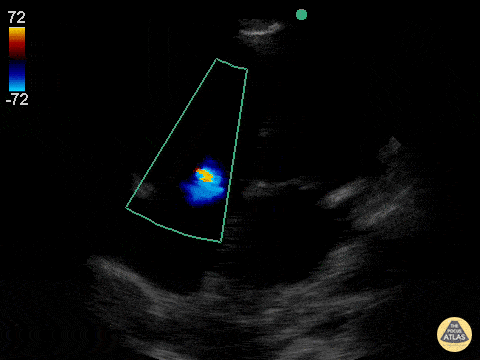

Valvulopathy - Mild Tricuspid Regurgitation

A narrow, central tricuspid regurgitation jet is seen on this apical 4-chamber view consistent with mild tricuspid regurgitation. Jason Tanguay, DO